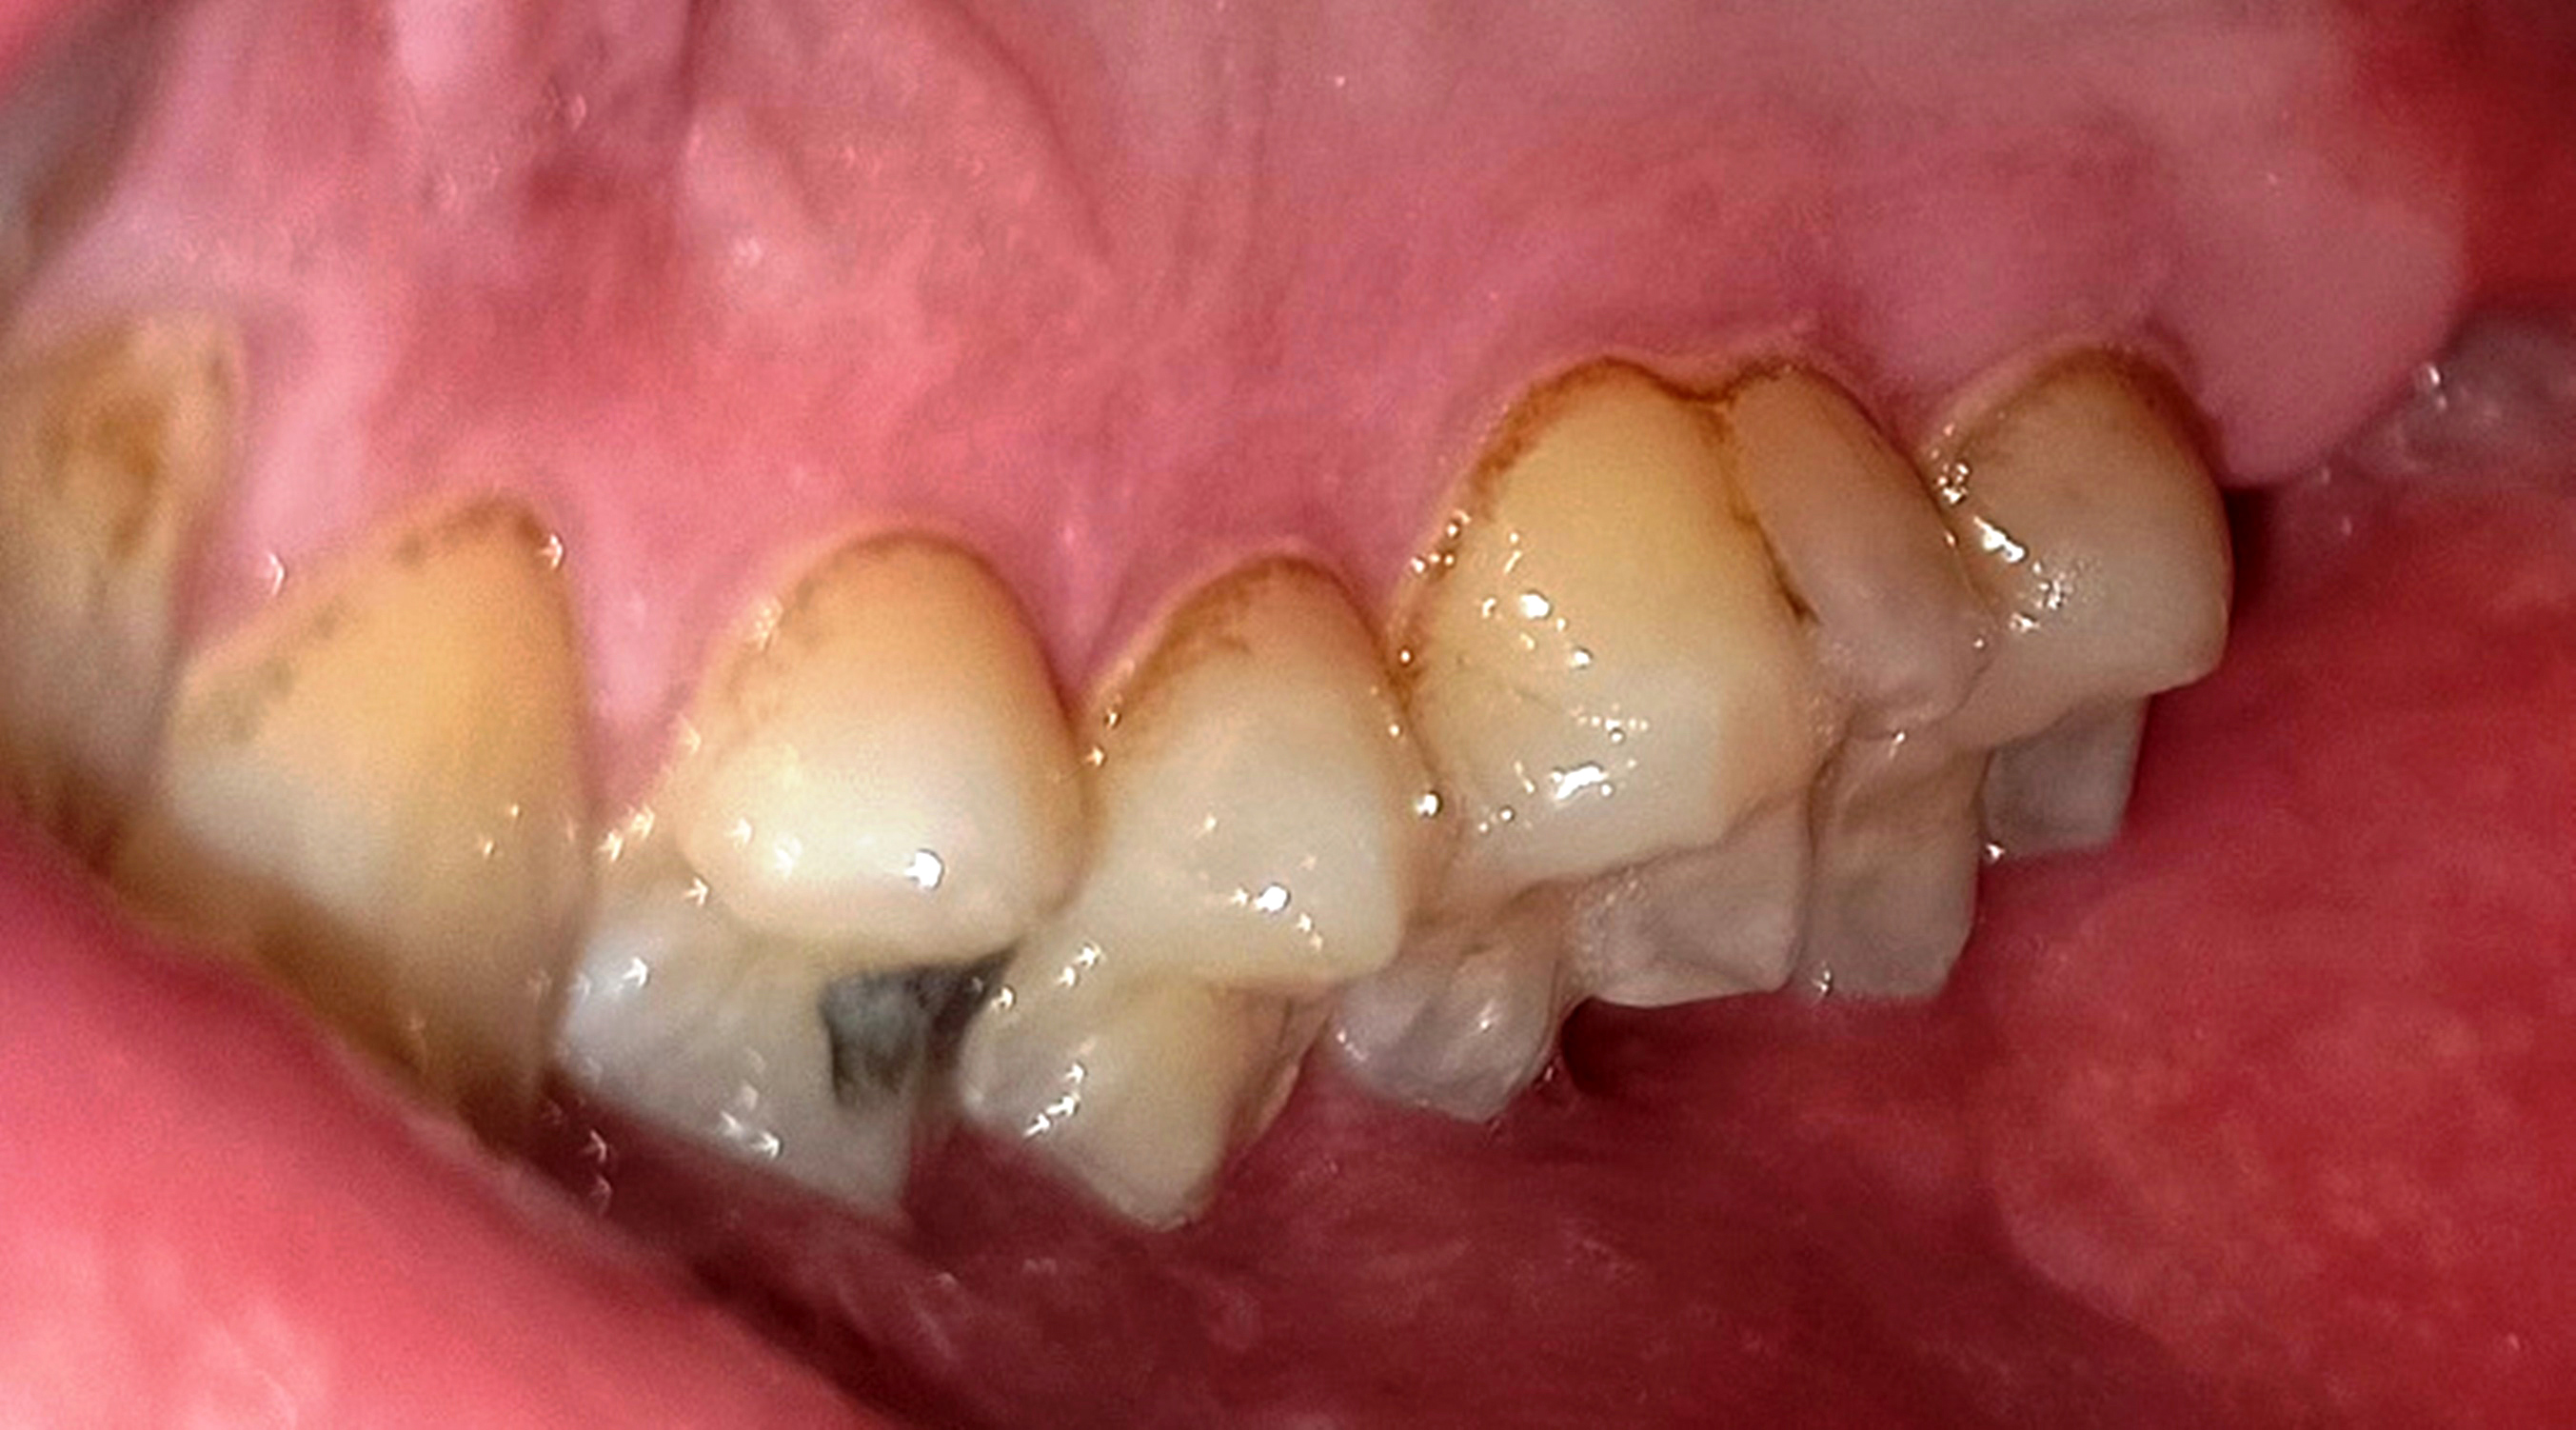

Innerhalb der Gruppe der Patienten mit Fazialisparese wurde außerdem ein Vergleich der Mundgesundheit zwischen beiden Mundhälften durchgeführt. Dabei wies die paretische Seite eine signifikant höhere Plaque-Kontamination, mehr Blutungen und höhere PSI-Werte auf als die nicht paretische Seite (Tab. 3). Die Plaque-Kontamination war in Bezug auf den API auf der paretischen Seite um 10,9 % (p = 0,004) höher als auf der nicht paretischen Seite. Ebenso wiesen die vestibulären Zahnoberflächen der paretischen Seite mehr Biofilm auf als die der nicht paretischen Seite (p = 0,002; s. Tab. 3, Abb. 2a und b). Dabei war der Unterschied bei den männlichen Patienten (0,8 vs. 0,5; p = 0,001) größer als bei den weiblichen Patienten (0,6 vs. 0,4; p = 0,002). Außerdem wurde bei Patienten mit rechtsseitiger Fazialisparese ein größerer Seitenunterschied (0,7 vs. 0,5; p < 0,001) dokumentiert als bei Patienten mit linksseitiger Fazialisparese (0,5 vs. 0,4; p = 0,043). Ursächlich erschien die Händigkeit der Patienten. Während bei Patienten mit linksseitiger Fazialisparese die Erkrankung auf der für Rechtshänder besser zu reinigenden Mundhälfte vorlag, waren rechtshändige Patienten mit rechtsseitiger Fazialisparese einer doppelten Belastung ausgesetzt (18). Die Gingivablutung nach Sondierung war auf der paretischen Seite ebenfalls signifikant höher als auf der nicht paretischen Seite (s. Tab. 3). Das spiegelte sich sowohl bei den Werten des SBI (s. Tab. 3, Abb. 3) als auch bei den Werten des PBI (s. Tab. 3, Abb. 4a und b) wider. Die Sondierungstiefen waren auf der paretischen Seite im Vergleich zur nicht paretischen Seite tiefer und der Attachmentverlust war höher. Dabei konnte jedoch kein signifikanter Unterschied nachgewiesen werden. Der mittlere PSI erreichte auf der paretischen Seite signifikant höhere Werte als auf der nicht paretischen Seite (p = 0,032; s. Tab. 3), was auf eine schlechtere Gingivagesundheit hinweist. Darüber hinaus war die Prävalenz unbehandelter kariöser Läsionen auf der paretischen Seite höher als auf der nicht paretischen Seite (s. Tab. 3). Ein Fallbeispiel illustriert eindrucksvoll die Unterschiede zwischen der kariesfreien nicht paretischen Seite und der paretischen Seite mit multiplen aktiv kariösen Läsionen (Abb. 5a und b). Zusätzlich wies die paretische Seite eine höhere Anzahl an Restaurationen auf als die nicht paretische Seite (s. Tab. 3). Hinsichtlich des Zahnsteinbefalls wurden auch im Seitenvergleich der Mundhälften keine signifikanten Unterschiede zwischen den paretischen und den nicht paretischen Seiten festgestellt. Im Einzelfall wurden jedoch eindrucksvolle Unterschiede zwischen den Mundhälften deutlich (Abb. 6a und b).